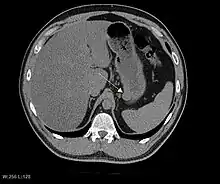

CT scanning is often undertaken (see the radiology section).

The purpose of radiologic imaging is to locate the lesion, evaluate for signs of invasion and detect metastasis. Features of GIST vary depending on tumor size and organ of origin. The diameter can range from a few millimeters to more than 30 cm. Larger tumors usually cause symptoms in contrast to those found incidentally which tend to be smaller and have better prognosis.[4][13] Large tumors tend to exhibit malignant behavior but small GISTs may also demonstrate clinically aggressive behavior.[14]

Barium fluoroscopic examinations and CT are commonly used to evaluate the patient with abdominal complaints. Barium swallow images show abnormalities in 80% of GIST cases.[14] However, some GISTs may be located entirely outside the lumen of the bowel and will not be appreciated with a barium swallow. Even in cases when the barium swallow is abnormal, an MRI or CT scan must follow since it is impossible to evaluate abdominal cavities and other abdominal organs with a barium swallow alone. In a CT scan, abnormalities may be seen in 87% of patients and it should be made with both oral and intravenous contrast.[14] Among imaging studies, MRI has the best tissue contrast, which aids in the identification of masses within the GI tract (intramural masses). Intravenous contrast material is needed to evaluate lesion vascularity.

Preferred imaging modalities in the evaluation of GISTs are CT and MRI,[16]: 20–21 and, in selected situations, endoscopic ultrasound. CT advantages include its ability to demonstrate evidence of nearby organ invasion, ascites, and metastases. The ability of an MRI to produce images in multiple planes is helpful in determining the bowel as the organ of origin (which is difficult when the tumor is very large), facilitating diagnosis.

As the tumor grows it may project outside the bowel (exophytic growth) and/or inside the bowel (intraluminal growth), but they most commonly grow exophytically such that the bulk of the tumor projects into the abdominal cavity. If the tumor outstrips its blood supply, it can necrose internally, creating a central fluid-filled cavity with bleeding and cavitations that can eventually ulcerate and communicate into the lumen of the bowel. In that case, barium swallow may show an air, air-fluid levels or oral contrast media accumulation within these areas.[14][17] Mucosal ulcerations may also be present. In contrast-enhanced CT images, large GISTs appear as heterogeneous masses due to areas of living tumor cells surrounding bleeding, necrosis or cysts, which is radiographically seen as a peripheral enhancement pattern with a low attenuation center.[13] In MRI studies, the degree of necrosis and bleeding affects the signal intensity pattern. Areas of bleeding within the tumor will vary its signal intensity depending on how long ago the bleeding occurred. The solid portions of the tumor are typically low signal intensity on T1-weighted images, are high signal intensity on T2-weighted images and enhanced after administration of gadolinium. Signal-intensity voids are present if there is gas within areas of necrotic tumor.[15][18][19]

Features of malignancy

Malignancy is characterized by local invasion and metastases, usually to the liver, omentum and peritoneum. However, cases of metastases to bone, pleura, lungs and retroperitoneum have been seen. In distinction to gastric adenocarcinoma or gastric/small bowel lymphoma, malignant lymphadenopathy (swollen lymph nodes) is uncommon (<10%) and thus imaging usually shows absence of lymph node enlargement.[13] If metastases are not present, other radiologic features suggesting malignancy include: size (>5 cm), heterogeneous enhancement after contrast administration, and ulcerations.[4][13][20] Also, overtly malignant behavior (in distinction to malignant potential of lesser degree) is less commonly seen in gastric tumors, with a ratio of behaviorally benign to overtly malignant of 3-5:1.[4] Even if radiographic malignant features are present, these findings may also represent other tumors and definitive diagnosis must be made immunochemically.